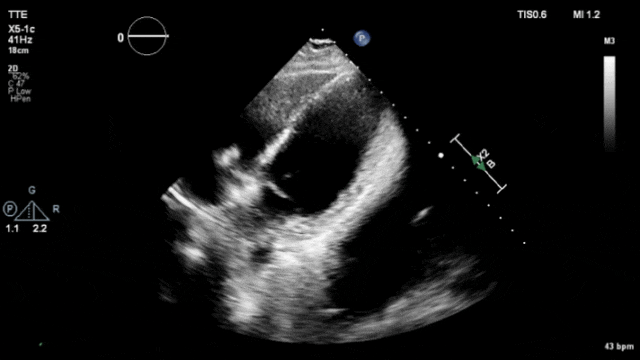

Video2:心尖四腔心切面(非标准)-牵拉测试确认起搏器锚定的稳定性及心包情况